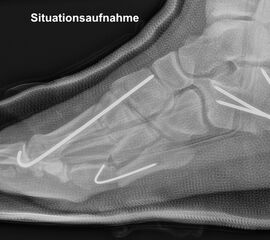

Abb. 3 a-j: Beispiel einer Calcaneusverschiebeosteotomie mit offenen Wachstumsfugen und der entsprechenden Osteosynthese mit Kirschner Drähten. Lokalisation der Osteotomie (a), Lage der Fräse (b-d), Drahtlage mehrere Ansichten (e-h), Heilung der Osteotomie 4 Wochen postoperativ und Entfernung der Drähte (i-j).

Calcaneus-Osteotomie

Die minimalinvasive Calcaneusverschiebeosteotomie bietet eindeutige Vorteile gegenüber dem offenen Verfahren, sodass wir bei Kindern und Jugendlichen nahezu keine offene Verschiebeosteotomie mehr durchführen. Am Calcaneus liegt die offene Wachstumsfuge dorsal. Bei der Durchführung müssen Schenkel der V-förmigen Osteotomie daher etwas steiler angelegt werden, in einem stumpfen Winkel (siehe Abb. 3 a-j). Für die Osteotomie liegen unsere Patienten auf dem Rücken und der BV wird für die exakte Seitaufnahme eingestellt. Der Fuß lagert auf einem hohen OP-Kissen und die Osteotomie kann bequem mit einem langen Kirschner-Draht und einem sterilen Stift angezeichnet werden (Abb. 15).